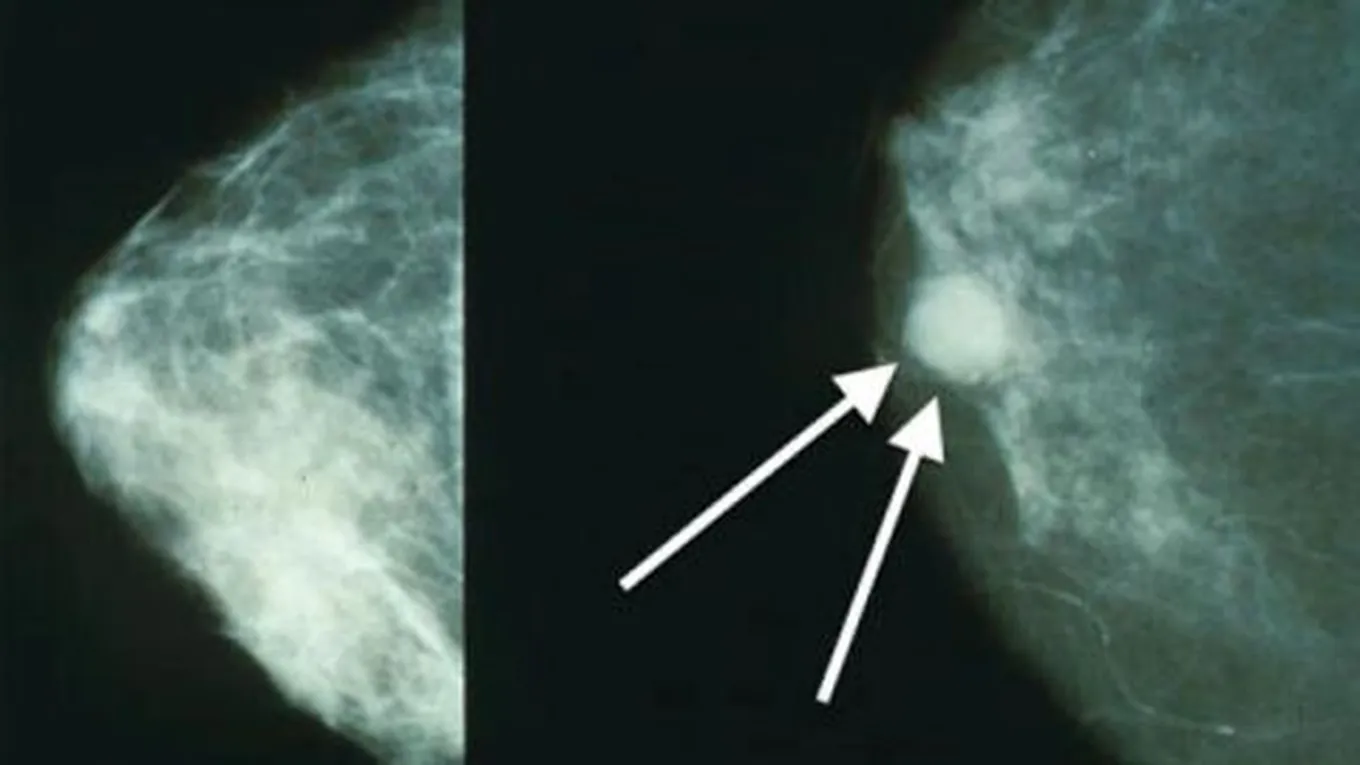

- ظهور كتلة صغيرة في الثدي أو حتى تحت الإبط، وهذه الكتلة غير مؤلمة في العادة.

الفحص الطبي

- الفحص باستخدام الأشعة السينية.